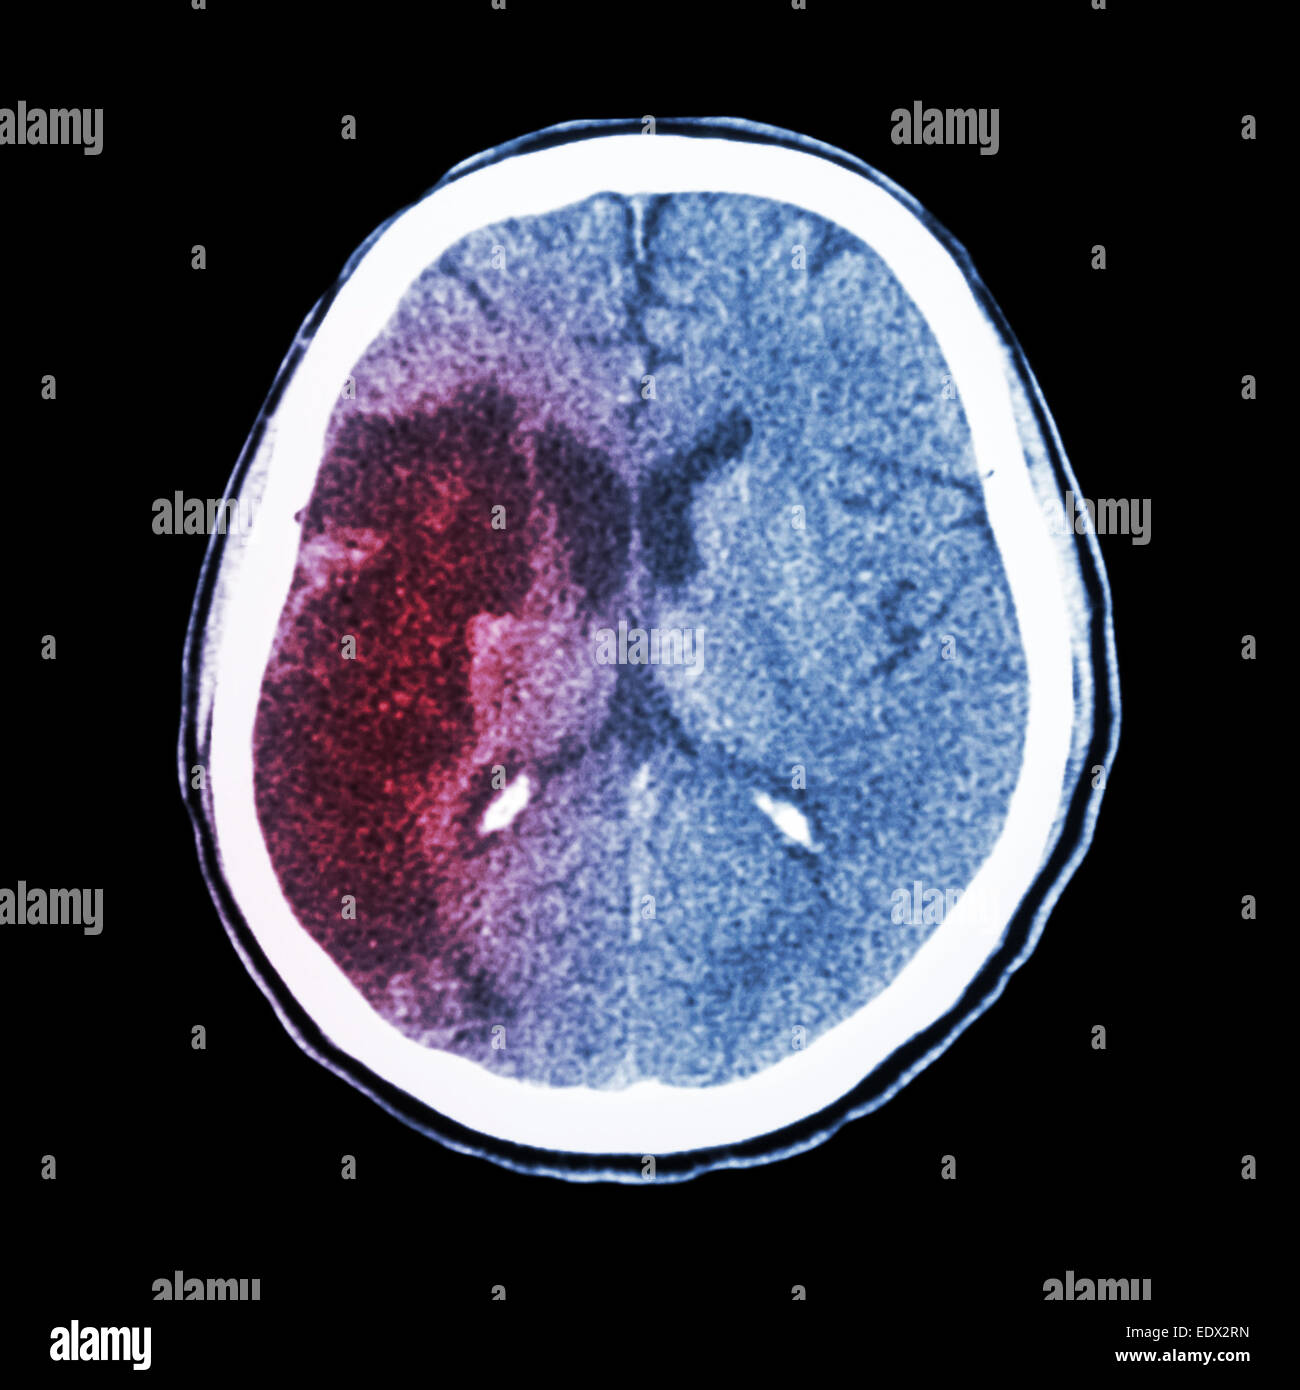

Tc brain : spectacle d'un accident vasculaire cérébral ischémique (hypodensite au-frontal droit lobe pariétal) Banque D'Imageshttps://www.alamyimages.fr/image-license-details/?v=1https://www.alamyimages.fr/photo-image-tc-brain-spectacle-d-un-accident-vasculaire-cerebral-ischemique-hypodensite-au-frontal-droit-lobe-parietal-77404983.html

Tc brain : spectacle d'un accident vasculaire cérébral ischémique (hypodensite au-frontal droit lobe pariétal) Banque D'Imageshttps://www.alamyimages.fr/image-license-details/?v=1https://www.alamyimages.fr/photo-image-tc-brain-spectacle-d-un-accident-vasculaire-cerebral-ischemique-hypodensite-au-frontal-droit-lobe-parietal-77404983.htmlRFEDX2RK–Tc brain : spectacle d'un accident vasculaire cérébral ischémique (hypodensite au-frontal droit lobe pariétal)